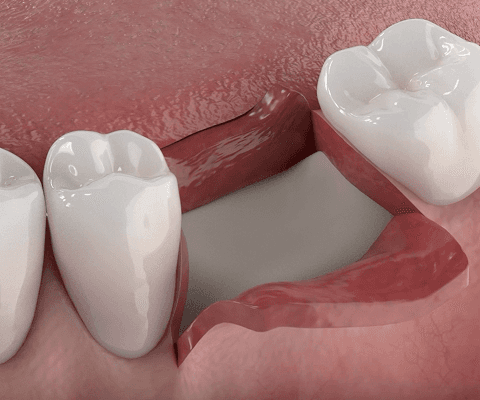

부족한 부위에 인공뼈 이식

잇몸뼈의 넓이나 높이가 부족한 부위에 인공뼈(골이식재)를 채워 넣어 임플란트를 식립할 수 있는 공간을 만듭니다.

03

이식한 뼈 위에 차폐막을 덮어 고정

차폐막은 이식한 뼈 위를 덮어 외부 자극이나 잇몸세포 침입을 막고, 뼈가 제대로 자랄 수 있도록 안정된 환경을 만들어줍니다.